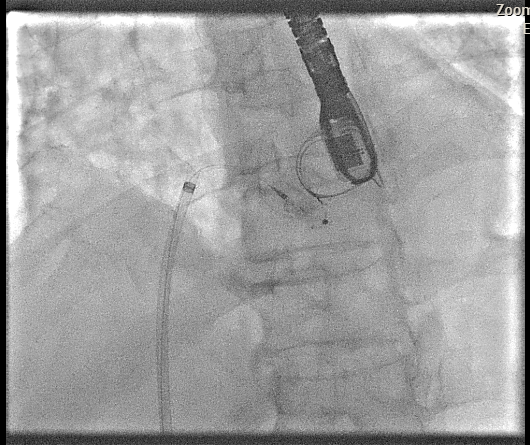

Transesophageal Echocardiography (TEE) EvaluationTEE was performed and demonstrated severe paravalvular leakage of the bioprosthetic mitral valve at the 3 o¡¯clock position.Vascular Access PreparationBoth groins were infiltrated with 10 mL of 2% lidocaine for local anesthesia. Using the front-wall technique, a 6F sheath was inserted into the right femoral vein and subsequently upsized to a 12F FastCath introducer sheath. The left femoral artery was cannulated with a 6F sheath for continuous arterial pressure monitoring.Transseptal PunctureA 0.032-inch guidewire was advanced into the superior vena cava, followed by placement of an 8.5F SL1 introducer. A BRK 18-gauge transseptal needle was introduced with the needle tip kept within the sheath.Under TEE and fluoroscopic guidance, the system was slowly withdrawn into the right atrium to identify the optimal puncture site. A successful mid-posterior transseptal puncture was achieved into the left atrium.Hemodynamics recorded LA pressure of 12 mmHg with a peak V-wave of 19 mmHg.Crossing the Paravalvular Leak (PVL)A 0.032-inch wire was advanced across the PVL, and the 8.5F Agilis catheter was positioned in the left atrium.Wire and Catheter Exchange for PVL CrossingA 6F MP01 guiding catheter was directed toward the medial aspect of the mitral valve. A 0.035-inch Terumo wire crossed into the left ventricle and was exchanged for an Amplatz Super Stiff wire.Sheath ExchangeThe 6F MP guiding catheter and 8.5F Agilis sheath were removed and replaced with a 7F DuraSheath (90 cm) to provide adequate support.First Attempt at PVL ClosureAn Amplatzer Vascular Plug III (AVP III) 5 ¡¿ 10 mm was delivered across the defect. Despite optimal positioning, the device did not achieve complete occlusion of the PVL.Successful PVL ClosureThe Trevisio 8F delivery system replaced the 7F DuraSheath. A larger AVP III 5 ¡¿ 14 mm device was advanced across the defect and deployed.After position adjustment, the device was released. TEE confirmed a stable device position with no residual PVL. All equipment was removed, and the venous access was upsized to a 14F FastCath introducer to prepare for LAA occlusion.Transition to LAA Occlusion PhaseA 10F Lambre delivery sheath was advanced into the left upper pulmonary vein (LUPV), replacing the SL1 sheath.Accessing the LAAA 5F pigtail catheter was inserted, and the delivery sheath was advanced into the LAA under fluoroscopic and TEE guidance.Device PreparationA 38/34 mm Lambre LAA occlusion device was prepared and loaded into the delivery system.LAA Occlusion DeploymentThe device was deployed just proximal to the LAA ostium. Stability and seating were confirmed using angiography and TEE.LAA angiography demonstrated trace residual flow into the LAA. The device was then detached.Real-time 3D TEE confirmed proper positioning with no significant peridevice leak.Hemostasis and CompletionAll delivery systems were removed. Venous hemostasis was achieved using a figure-of-eight suture, and arterial access was sealed with manual compression. The procedure was completed without immediate complications.